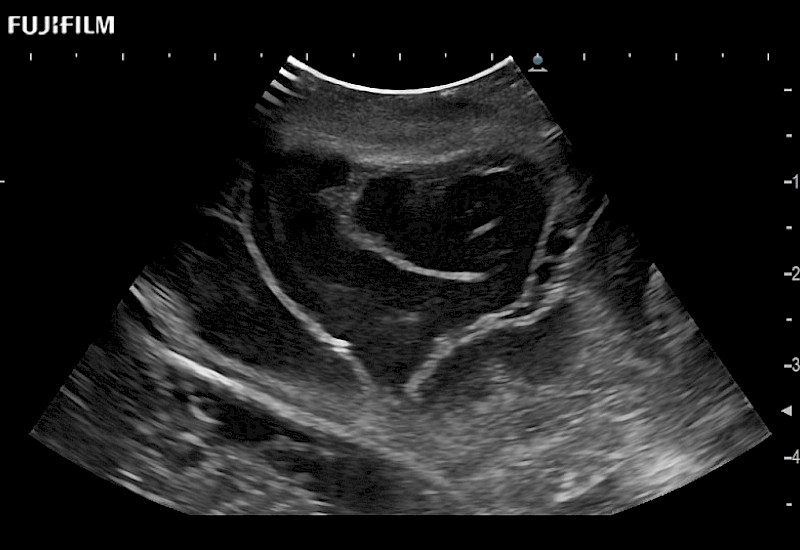

The world's only phased array burr-hole transducer that is ideal for scanning during burr-hole guidance procedures.

Main Specifications: